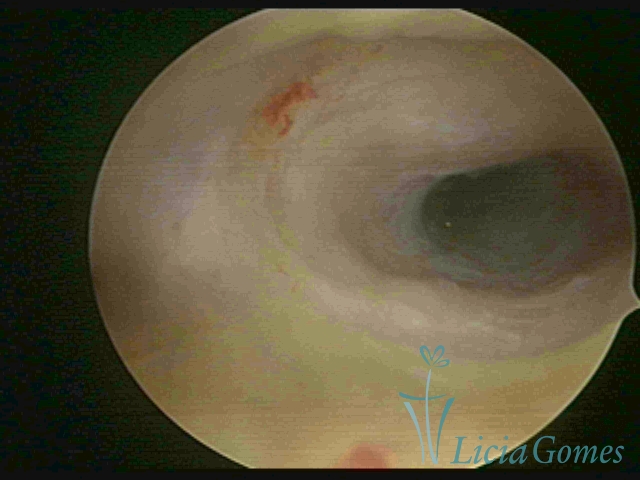

Third part or upper section

Presents the mucosa with a smooth, poorly vascularized surface, to the internal orifice